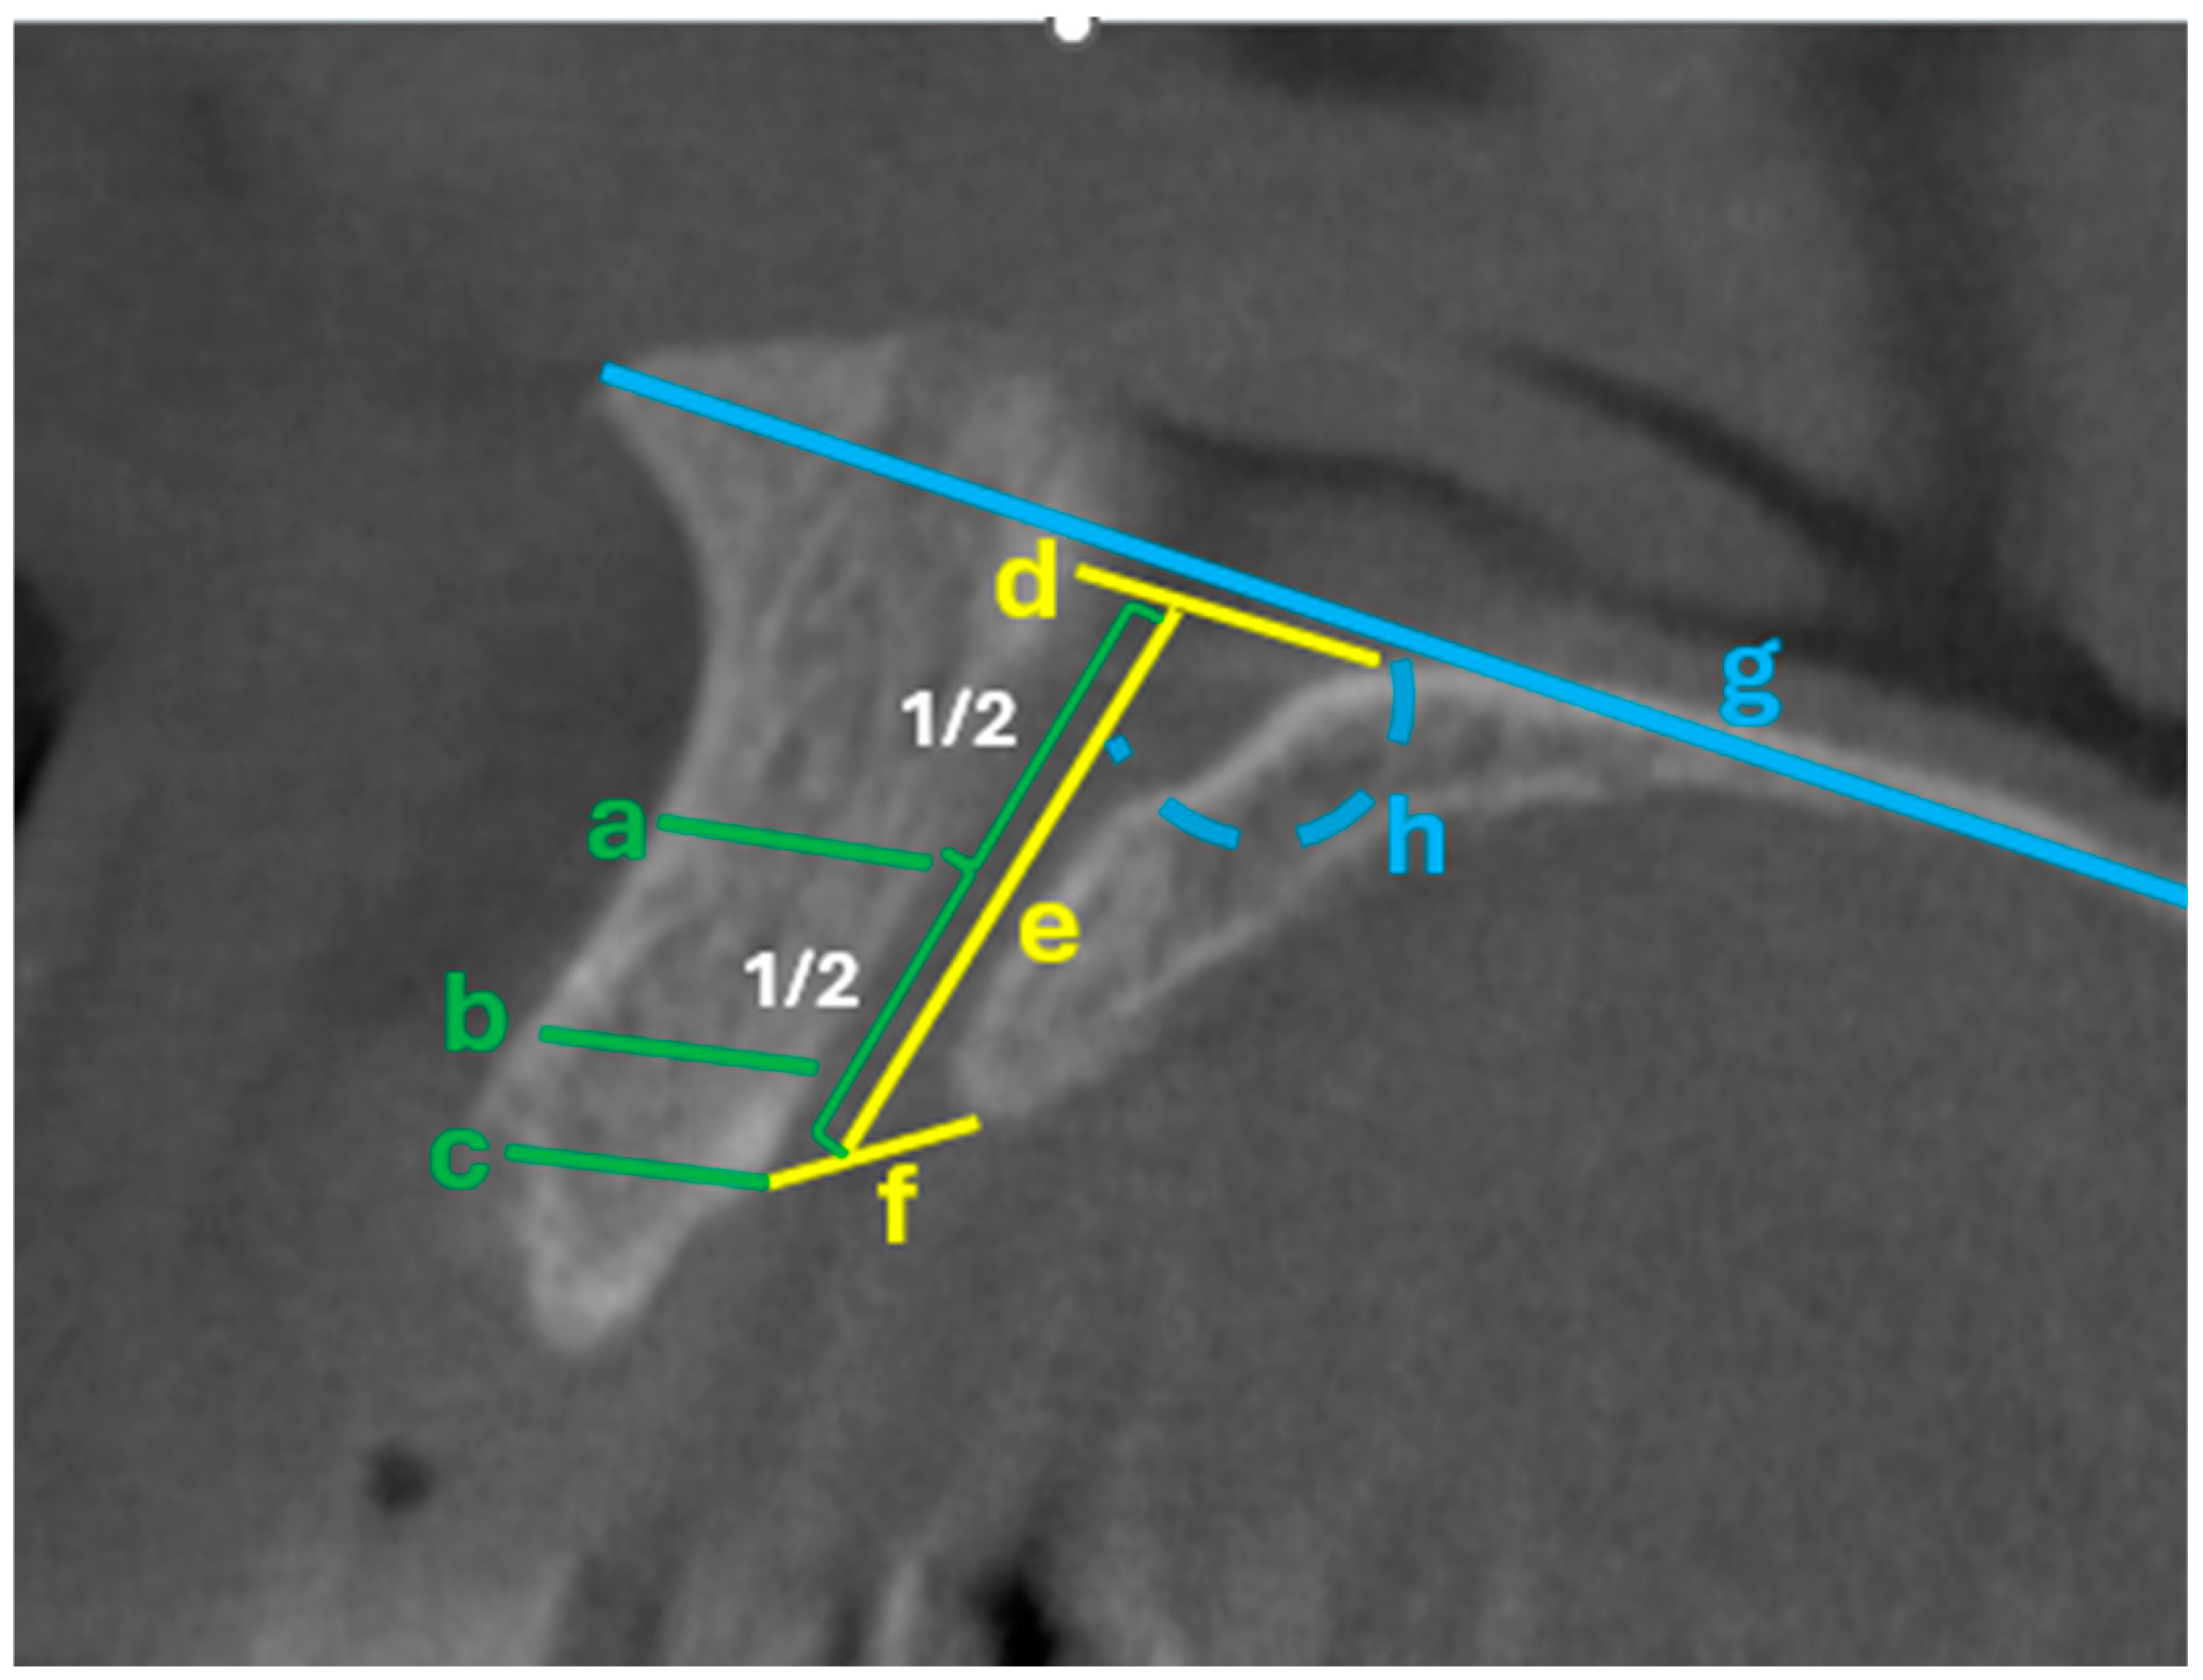

- Quantify proximity: Report Bw-pre 1/2/3 values and flag the lowest quartile—or a validated conservative threshold—as indicating heightened-risk proximity. Previous morphometric studies have demonstrated that the mean bone width between the central incisor root and the NPC ranges from approximately 1.4 mm at the coronal third to 3.2 mm at the apical third [9,10]. Accordingly, the risk of NPC perforation becomes clinically significant when the distance between the canal and the planned implant trajectory is less than 2 mm.

- Assess canal trajectory (Angle 1): Markedly oblique canals reduce the safe implant window; consider a more palatal entry point or a custom sleeve offset to prevent encroachment.

| Angle 1 (with horizontal plate) | 107.50 | 4.43 | |

| Angle 2 (with palatal bone margin) | 6.35 | 1.81 | |

| Angle 3 (with incisor) | 9.26 | 3.48 | |

| Bw-pre 1 (mm) | 1.66 | 0.45 | |

| Bw-pre 2 (mm) | 2.53 | 0.58 | |

| Bw-pre 3 (mm) | 3.59 | 0.82 |